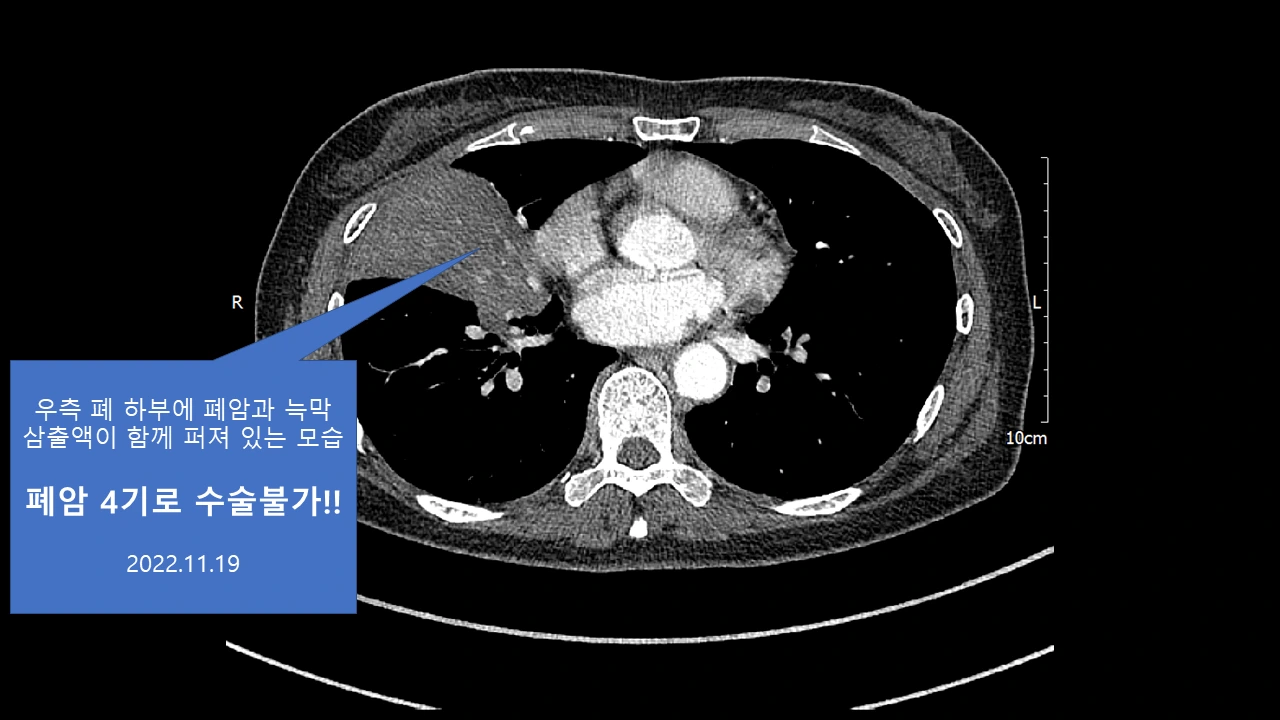

아래 또 다른 폐암 4기 환우분의 스토리도 너무 감동이라... 의사 선생님이 쓰신 글을 허락 없이 퍼왔다.